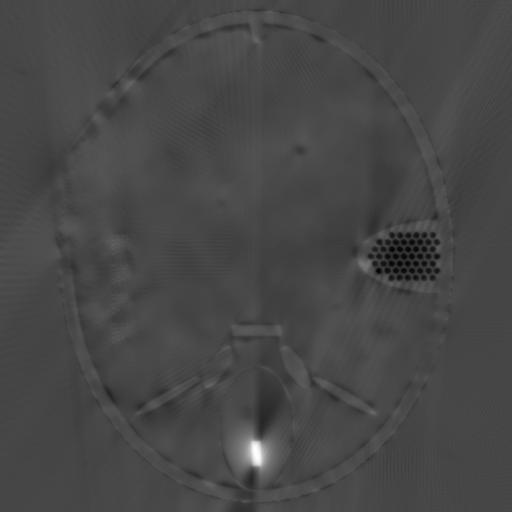

Fig.4 shows the limited-angle CT reconstruction results of the Forbild phantom using different methods, where the projection angle goes from to with increments. Fig.4a presents the reconstruction result of the steepest descent algorithm. Due to the missing projections, the reconstruction result suffers from severe artifacts. Fig.4b shows the result of the CDIP algorithm using Fig.4a as input. It is evident that CDIP cannot remove the existing artifacts in Fig.4a and, in fact, further degrades the reconstruction accuracy. On the contrary, the output of the original DIP method (Fig.4c) significantly suppresses the artifacts and achieves a much better result. Finally, Fig.4d shows the reconstruction result of our proposed method (SDIP), which is very close to the ground truth. Its details will be introduced in Section III-C.

(a) Steepest Descent (23.29dB)

(b) CDIP (19.82dB)

(c) DIP (29.88dB)

(d) SDIP (38.61dB)